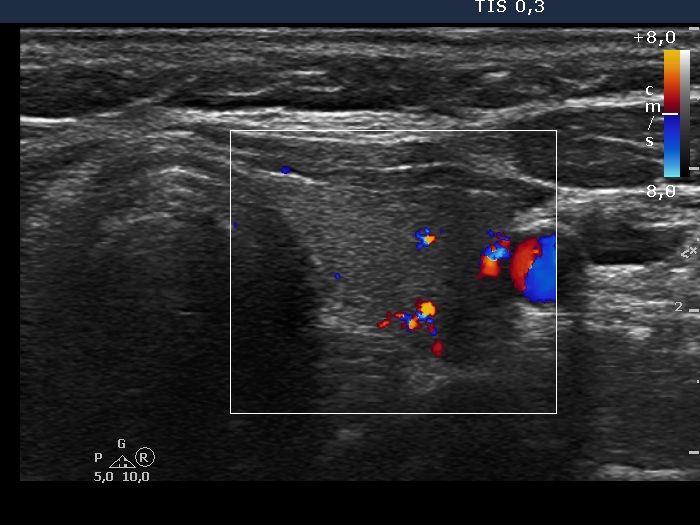

6 months after initial investigation (ultrasonographic picture 6)

Left lobe, transverse scan, color Doppler method. The vascularization is average.